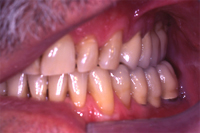

Um den Kieferkamm zu verbreitern, habe ich aus der hinteren Unterkieferregion drei Knochenstücke entfernt und sie mit je einer 9 bzw. 7 mm langen Schraube vorne seitlich fixiert (Abb. 3). Nach einer fünfmonatigen Einheilungszeit wurden die drei Fixationsschrauben entfernt und gleichzeitig zwei Implantate gesetzt (Abb. 4). Da der Knochen transversal üppig breit war, konnte ich zwei Straumann Implantate mit dem grössten Durchmesser von 4.8 mm setzen. Die Metallkeramikbrücke wurde vier Monate später zementiert.